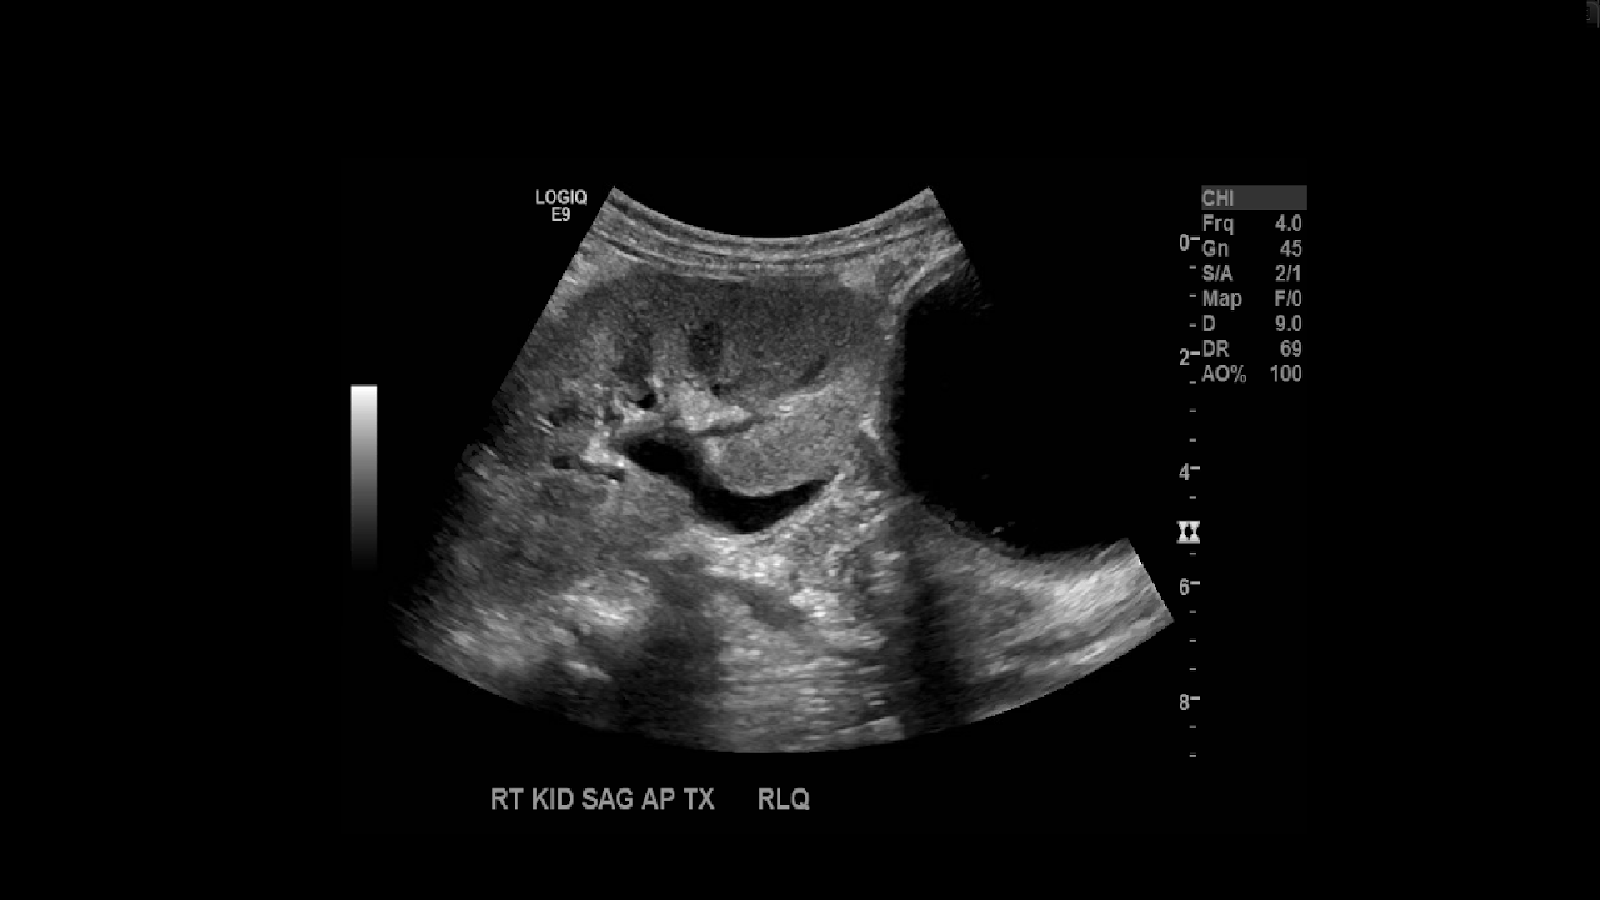

Next proceed to evaluate the transplanted kidney. The most common site of implantation is in the right iliac fossa.

In full sized adults you’ll observe the kidney in the right iliac fossa. Image the kidney in sagittal and transverse planes. Utilize Doppler to see the vascularity. Measure the kidney. If the kidney is too large you can take a panoramic image. Make sure to take not of the echogenicity, check for edema, areas of no vascularity, look for collections.